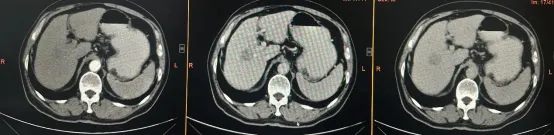

李大爷的肿瘤正好位于肝脏的Ⅴ、Ⅷ段交界处,紧邻门静脉的右前支与右后支分叉部,属于典型的、手术风险极高的中央型肝癌。

640 (1)_副本

640 (2)_副本